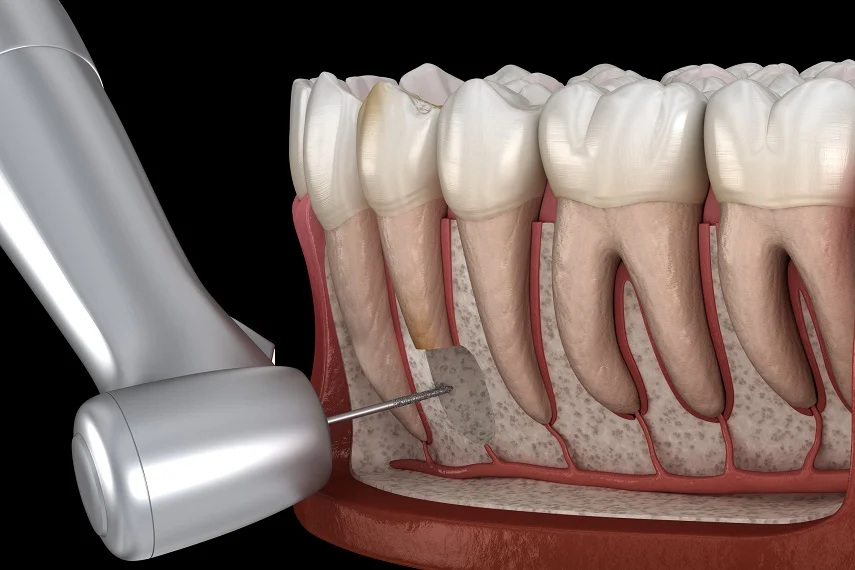

Zdjęcie RTG pokazuje, że kanał istnieje. Tomografia CBCT pokazuje, ile kanałów naprawdę jest, gdzie biegną, gdzie się rozgałęziają i czy zmiana periapikalna obejmuje wyłącznie wierzchołek korzenia – czy sięga głębiej. Tomografia CBCT zębów to badanie trójwymiarowe dedykowane diagnostyce endodontycznej, ocenie zmian okołokorzeniowych, resorpcji korzeni i lokalizacji zębów zatrzymanych. Jeden plik DICOM dostarcza danych, których żadna projekcja 2D nie zastąpi. Umów diagnostykę CBCT i uzyskaj pełny obraz sytuacji klinicznej przed decyzją o leczeniu.

- Ile kanałów ma Twój ząb i gdzie dokładnie biegną – lekarz widzi to w 3D zanim zacznie leczenie; kanały dodatkowe i skrzywienia niewidoczne na zwykłym zdjęciu RTG nie są niespodzianką podczas zabiegu

Anatomia kanałów korzeniowych w 3D – liczba, przebieg i skrzywienia przed leczeniem kanałowym

Tomografia CBCT zębów z małym polem widzenia pokazuje układ kanałowy bezpośrednio: lekarz widzi liczbę kanałów, ich wzajemną relację, kąt skrzywienia w każdej z trzech płaszczyzn i odległość wierzchołka od anatomicznych struktur granicznych. Dla zębów wymagających powtórnego leczenia kanałowego CBCT ujawnia miejsca, gdzie poprzednie leczenie nie dotarło – boczne odgałęzienia, nieuzbrojone kanały, ślepy zaułek pominięty w pierwotnym leczeniu.

Planowanie leczenia kanałowego w oparciu o CBCT skraca czas zabiegu i zmniejsza ryzyko pominięcia kanału – głównej przyczyny niepowodzeń endodontycznych prowadzących do konieczności powtórnego leczenia lub ekstrakcji. Dane z badania przekazywane są lekarzowi prowadzącemu w formacie DICOM gotowym do otwarcia w dowolnym oprogramowaniu endodontycznym.

- Liczba kanałów w 3D – rzeczywista anatomia kanałowa widoczna bezpośrednio; zidentyfikowanie kanałów dodatkowych i bocznych odgałęzień przed rozpoczęciem leczenia

- Kierunek i kąt skrzywienia korzenia zmierzony dokładnie – lekarz dobiera narzędzia i technikę leczenia do rzeczywistego kształtu kanału, nie szacuje go z płaskiego zdjęcia

- Zwężenia i zarosty kanału widoczne przed leczeniem – lekarz wie z góry, czy instrumentacja jest możliwa, czy konieczne jest podejście chirurgiczne

- Gdzie poprzednie leczenie nie dotarło – pominięte kanały i odgałęzienia widoczne od razu przy diagnostyce przed ponownym leczeniem; brak domysłów co do przyczyny niepowodzenia